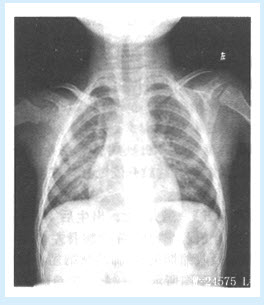

患儿,男,3岁,发热、咳嗽、咳痰1天。查体:双肺可闻及湿啰音。X线平片如图所示。

(单选题)最可能的诊断是()

A:大叶性肺炎

B:血行播散型肺结核

C:过敏性肺炎

D:支气管肺炎

E:原发综合征

F:以上都不是